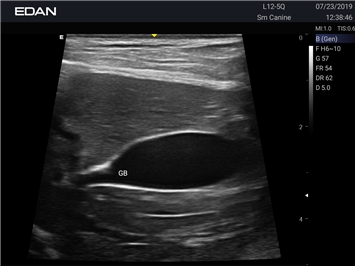

Ветеринарный ультразвук одним нажатием. Система Acclarix AX2 VET разработана с целью обеспечить бескомпромиссную производительность по доступной цене. Наличие уникальных двойных аккумуляторов в легком корпусе массой 4,5 кг из магниевого сплава позволяет системе Acclarix AX2 VET удовлетворять все потребности ветеринарных исследований, сохранив низкую стоимость.

EDAN Acclarix AX2 VET представляет собой специализированную ветеринарную ультразвуковую систему, сочетающую высокую производительность с доступной ценой. Благодаря продуманной конструкции и передовым технологиям, система обеспечивает качественную диагностику животных различных видов.

• Предустановленные протоколы для различных видов животных

B-режим, Двухмерное сканирование:

Да